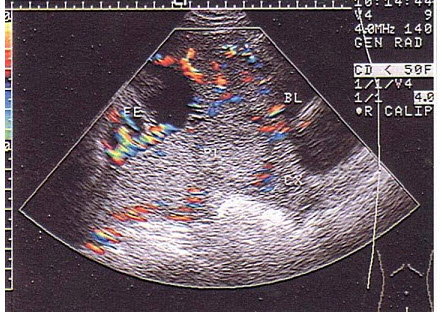

45、单项选择题

如图,初步超声诊断为()